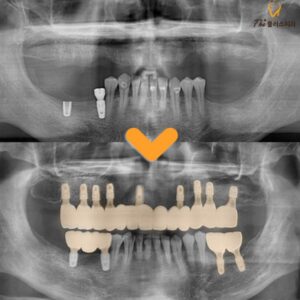

27. 수암동치과 교합 균형이 무너진 상태라면

수암동치과 교합 균형이 무너진 상태라면 [목차] ✔️ 초진 구강 상태와 치아 상실 확인 ✔️ 치료 방향 설정과 신경치료 진행 ✔️ 임플란트 식립 및 뼈유착 과정 ✔️ 보철 수복과 교합…